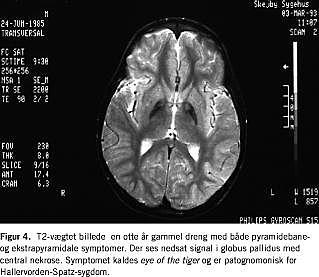

Antallet af metaboliske og degenerative sygdomme er mangfoldigt, hvorimod den enkelte sygdom er sjælden. MR-skanning har en stigende rolle i udredningen af disse [8]. Ud fra det kliniske billede kan klinikeren få mistanke om, at den grå eller den hvide substans er primært afficeret, og om at sygdommen primært involverer hemisfærerne, cerebellum eller måske basalganglierne (Figur 4 ). Med MR-skanning kan man påvise fordelingen af eventuelle strukturelle forandringer, hvilket sammen med de kliniske fund kan danne en solid basis for en snæver supplerende metabolisk eller genetisk udredning. En supplerende spektroskopi kan give vigtige informationer, der indsnævrer de diagnostiske stier yderligere. Nogle af de degenerative sygdomme, hvoraf ikke alle kan påvises ved gentest eller biokemiske analyser, udviser særlige signalændringer, hvor specifikke MR-skanningsfund kan være patognomiske og derfor medvirkende til, at man kan stille en sjælden diagnose in vivo [4, 9]. Fører MR-skanningen ikke primært til en endelig diagnose, kan man ofte med fordel gentage skanningen 1-2 år senere.